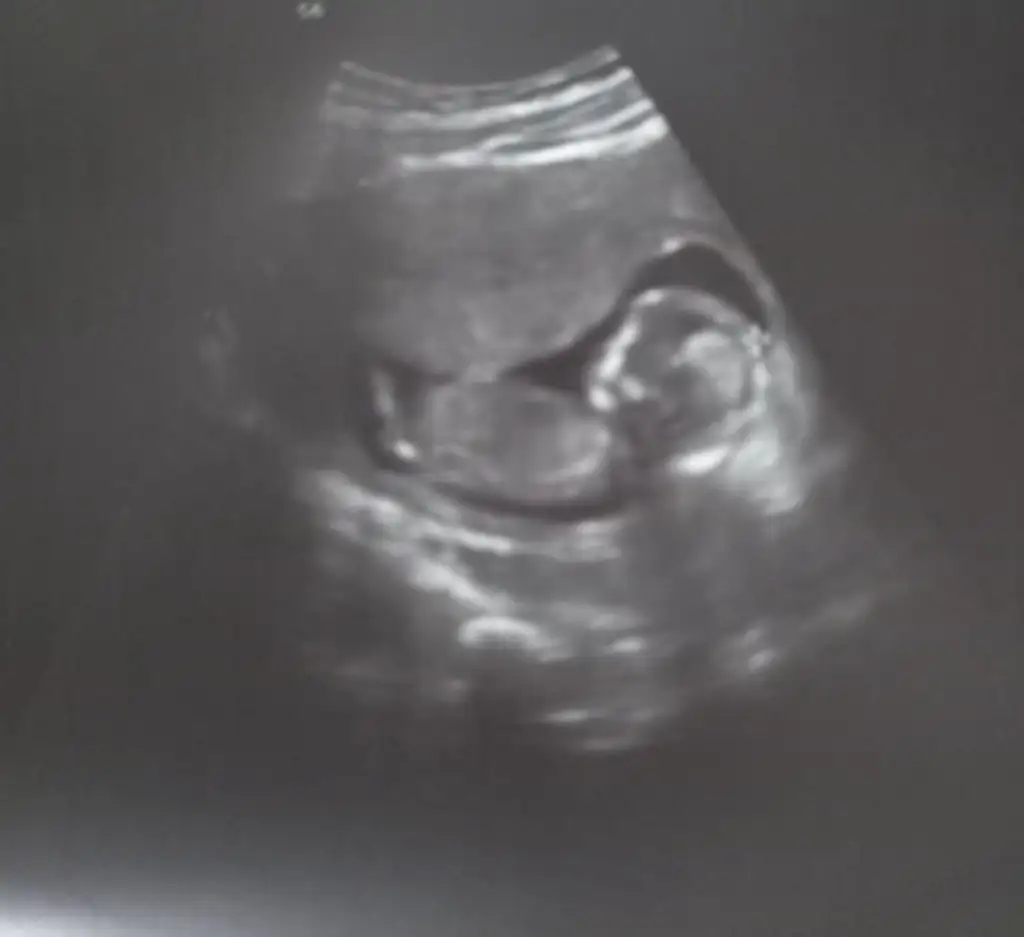

Yaa banada bakarmisiniz 10+3 vajinal bakıldı bugün 🙏🥰

Eklentiler

• IMG-20220427-WA0038.webp

IMG-20220427-WA0038.webp

11,4 KB · Görüntüleme: 94